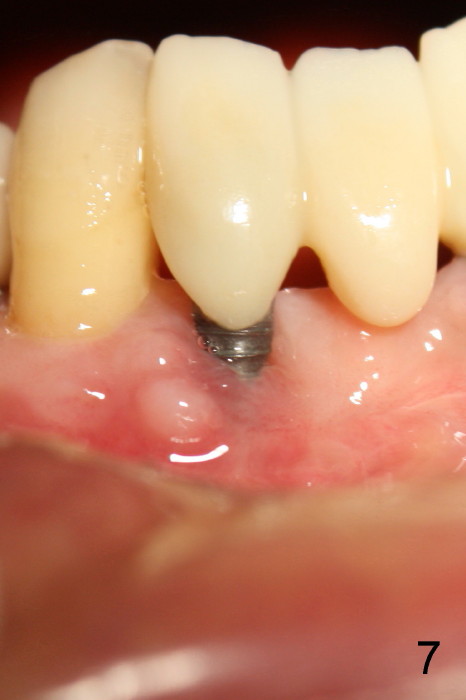

The patient has had chronic pain and swelling associated with the implant at the site of #26 (Fig.1). The extent of implant thread exposure is shown in Fig.2 after flap reflection; inflammatory granulation tissue is present around the most coronal threads (*, one year post cementation). Following debridement and Clindamycin soaking, allograft is placed around the exposed threads; a titanium mesh is used to contain the graft (Fig.3). The flap is closed with tension in spite of the periosteum being underscored. The patient develops moderate to severe ecchymosis postop.

Fig.5 is taken following local anesthesia to show the exposed mesh, 22 days post placement. When the latter is removed, the exposed threads appear to be less (Fig.6, as compared to Fig.2). There is healthy granulation tissue growth apically (*). The patient is asymptomatic 1 month post mesh removal; there is no tenderness around exposed threads (Fig.7). Connective tissue graft is planned to cover the exposed threads through tunnel technique. Thread exposure appears less 3 months post mesh removal (Fig.8). There is infection when the region is not kept clean (Fig.9 (2.5 years post mesh removal)). The other 1-piece implant should have minor implant exposure (<). It appears that there is no thread exposure associated with the immediate implant at #28. Using smaller 1-piece implants (2.5 or 2.0 vs. 3 mm) with flap surgery should be able to prevent the complication. The 72-year-old phobic patient declines any further treatment. Two years later, she agrees to have treatment because of repeated infection (Fig.10). Impression has been taken for stent. After sectioning FPD and removing the infected implant (Tatum), a smaller implant will be placed in between the implants. If her vein is not too small, blood will be drawn for PRF.